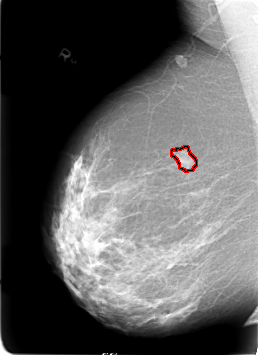

B_3020_1.RIGHT_MLO

RIGHT_MLO LINES 5680 PIXELS_PER_LINE 4120 BITS_PER_PIXEL 12 RESOLUTION 50 OVERLAY

FILE: B_3020_1.RIGHT_MLO.OVERLAY

TOTAL_ABNORMALITIES 1

ABNORMALITY 1

LESION_TYPE MASS SHAPE LOBULATED MARGINS CIRCUMSCRIBED-ILL_DEFINED

ASSESSMENT 4

SUBTLETY 4

PATHOLOGY MALIGNANT

TOTAL_OUTLINES 1

BOUNDARY